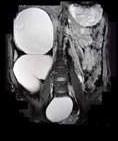

问题 女,28岁,持续性腰痛加重2天,伴尿频、尿急、尿痛及发热,MRI如图所示,下列说法正确的是 ( )

选项 A、考虑为输尿管癌所致的梗阻积水 B、考虑为输尿管囊肿 C、考虑为先天性巨输尿管 D、考虑为输尿管下端结石并积水 E、单侧输尿管明显扩张,同侧的肾盂肾盏也扩张,但其程度轻于前者

答案 CE